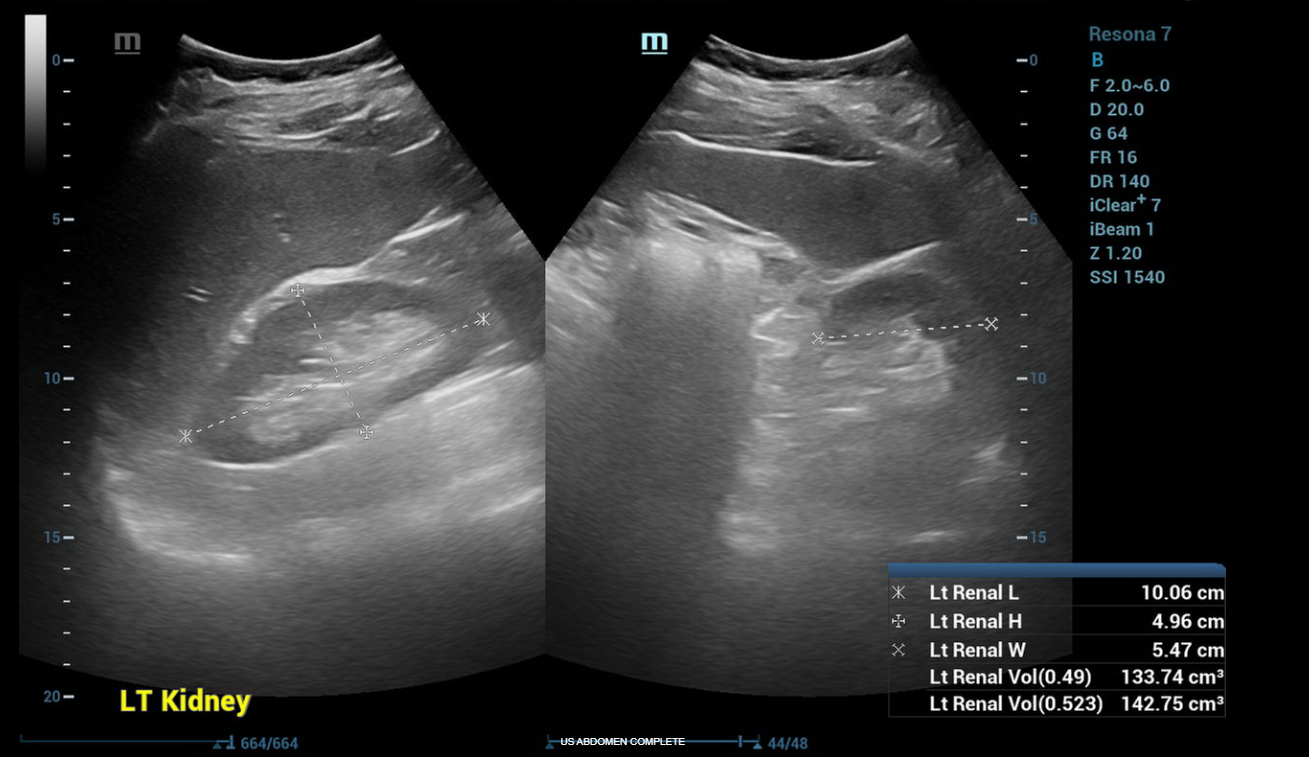

ULTRASOUND ABDOMEN GENERAL